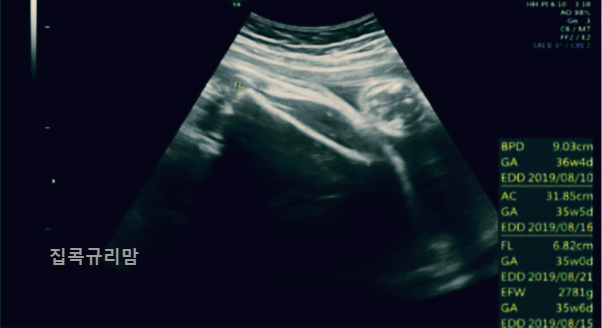

오늘은 태아초음파 아기초음파 용어에 대해 포스팅하려고 하는데요, 임신하게 되면 주기적으로 병원에서 초음파를 보는데 여러 용어들이 가득한 초음파를 볼 수 있습니다. 계속 초음파를 보다보면 용어가 궁금해지더라고요. 첫째 때 공부(?)를 하긴 했는데 역시나 기억이 사라져서 ㅎㅎ 'EDD'정도만 기억에 남아있는 제 모습을 발견했습니다. ㅎㅎ

초음파 용어가 엄청 많은데요, 가장 자주 볼 수 있는 용어들 위주로 정리하겠습니다.

GA(Gestational Age)

임신 주수로 W는 주수를, D는 날짜를 뜻합니다.

예시: 6w3d (6주 3일)

EDD (Expected Date of Delivery)

GA를 기준으로 산출한 출산 예정일로 GA와 EDD는 태아 크기에 따라 매번 달라질 수 있는데, 보통 임신 12주 미만에 정해진 임신 주수와 분만 예정일을 기준으로 태아 성장을 평가합니다.

AC(Abdominal Circumference)

복부 둘레 수치로 태아의 발육 상태를 확인할 수 있습니다.

BPD(Biparietal Diameter)

아두대횡경, 위에서 본 태아 머리 단면의 가장 긴 길이를 말합니다.

FL(Femur Length)

태아의 대퇴골(허벅지 뼈) 길이로 성장 발달 정도를 판단합니다.

EBW(Estimated Body Weight): 태아의 현재 체중을 확인합니다.